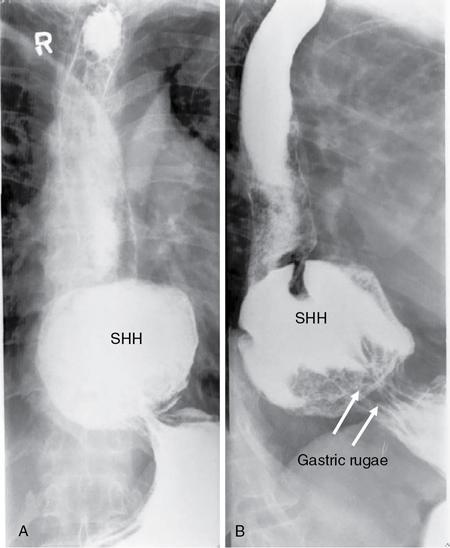

Swarup Nellore, Soumil Vyas, Ujwal Bhure, Ankit Jain, Richa Kothari, Daksh Mehta, Divya Kantesaria, Disha Lokhandwala, Karthik Ganesan The stomach is the most dilated portion of the gastrointestinal tract positioned between the oesophagus and the small intestine occupying the epigastrium, left hypochondrium and umbilical regions of the abdomen performing a multitude of functions including storage and mixing of food and controlling the passage of food into the intestine. Anatomically, the stomach is divided into the following parts (Fig. 8.2.1): the gastric cardia is the portion immediately adjoining the oesophageal opening into the stomach. The fundus is the dome-shaped part above the horizontal plane of the cardiac orifice which undergoes receptive relaxation and is the site of the autonomic pacemaker. The body is the largest part of the stomach extending from the cardiac orifice to the level of incisura angularis (notch like bend in the mid lesser curvature) containing majority of parietal cells (which secrete hydrochloric acid), chief cells (pepsinogen) and enterochromaffin-like cells (ECL). The pylorus is the tubular distal portion of the stomach which is further divided into the gastric antrum and pyloric canal. The pyloric antrum containing G-cells producing gastrin extends from the incisura angularis up to the pyloric sphincter which is an anatomical sphincter formed by concentric thickening of the circular muscle coat and encircles the narrow-slit like pyloric canal. The left dome of diaphragm and oesophagus lie superior to the stomach while the greater omentum and pancreas lie inferiorly. Spleen and liver lie on either side laterally while the transverse mesocolon is located inferolaterally. Diaphragm, greater omentum, left lobe of liver and anterior abdominal wall are anteriorly related to the stomach and contents of lesser sac including pancreas, spleen, splenic artery, transverse mesocolon, left kidney and adrenal gland lie posteriorly. The stomach is embryologically derived from the primitive foregut and is suspended anteriorly by the ventral mesogastrium and posteriorly by the dorsal mesogastrium. During development as the stomach rotates, the peritoneum grows and condenses to form perigastric ligaments, which contain blood vessels, lymphatics, lymph nodes, nerves and fat. The liver forms in the ventral mesogastrium, which develops into the falciform ligament, gastrohepatic ligament (GHL) and hepatoduodenal ligament (HDL). The spleen and pancreas form within the dorsal mesogastrium, which fuses with the posterior abdominal wall to form the gastrocolic ligament (GCL), gastrosplenic ligament (GSL) and splenorenal ligament (SRL). The perigastric ligaments are identified anatomically by the vessels contained in them (Fig. 8.2.2). The gastric cardia and lesser curvature of the stomach are attached to the inferior surface of liver by the lesser omentum by the gastrohepatic ligament respectively which contains the left and right gastric vessels. The inferior free edge of the gastrohepatic ligament extends inferiorly as the hepatoduodenal ligament between the porta hepatis and proximal duodenum gastrophrenic ligament extends between the stomach and the left hemidiaphragm. The gastrocolic ligament identified by the left and right gastroepiploic vessels, connects the greater curvature of the stomach to the anterior surface of the transverse colon. This ligament extends inferiorly as the greater omentum which is a double-layered peritoneum forming a drape anterior to the bowel loops. The gastrosplenic/lienogastric ligament bridges the posterolateral wall of the fundus and greater curvature along the proximal body of the stomach to the splenic hilum and contains the short gastric vessels. The gastrosplenic ligament is contiguous with the lienorenal ligament and both these structures constitute the lateral boundary of the lesser sac. Macroscopically the stomach shows a thick vascular mucosal lining in the form of longitudinal folds called gastric rugae. Microscopic layers of the stomach include mucosa, submucosa, muscularis externa and serosa. The mucosa includes surface mucus cells with simple columnar epithelium, gastric pits, gastric glands, lamina propria and muscularis mucosa. Submucosa includes connective tissue with submucosal Meissner’s plexus. Muscularis externa comprises three smooth muscle layers (longitudinal, circular and oblique) and Auerbach myenteric plexus. The outermost layer called serosa consists of loose connective tissue and visceral peritoneal lining. The arterial supply of stomach is constituted by the branches of celiac artery predominantly in the form of two anastomotic arcades along the lesser and greater curvature. Left gastric artery, a direct branch of the celiac trunk supplies the upper part of the lesser curvature while the lower part is supplied by the right gastric branch of the common hepatic artery arising at the upper border of pylorus. The left gastroepiploic artery, a branch of splenic artery, supplies the upper part of greater curvature and the inferior portion is supplied by the right gastroepiploic artery which is a branch of the gastroduodenal artery. The fundus additionally receives few small short gastric branches from the splenic artery. The veins follow the arteries in their nomenclature. Left and right gastric vein show direct drainage into the portal vein. The splenic vein derives flow from the short gastric and left gastroepiploic vein whereas the right gastroepiploic vein drains into the superior mesenteric vein. Pylorus can be surgically delineated by the prepyloric vein of Mayo lying on its anterior surface. Intrinsic nerve supply consists of the myenteric plexus of Auerbach and submucosal plexus of Meissner. Extrinsic nerve supply consists of sympathetic and parasympathetic components. Sympathetic nerve supply arises from T5 to T9 spinal cord segments supplying the celiac plexus via the greater splanchnic nerve. The plexuses then travel along the respective branches of celiac artery supplying the stomach. Parasympathetic nerve supply is derived from oesophageal plexus of vagus dividing into two vagal trunks. Right (posterior) vagus gives off the posterior gastric branch also called the criminal nerve of Grassi supplying the cardia and fundus of stomach. Right vagus then gives off a celiac branch and continues along lesser curvature of stomach as the posterior gastric nerve of Latarjet supplying the antrum, body and pylorus. Left (anterior) vagus gives off a hepatic branch then continues along the lesser curvature as the anterior nerve of Latarjet supplying the antrum, body and pylorus. Crow’s feet innervation to antropyloric area are important surgical landmarks preserved during highly selective vagotomy receiving branches from both major nerve trunks (anterior and posterior) at the incisura angularis. Anatomical lymphatic drainage is divided into three areas. Area I is the superior two-thirds of stomach draining via the nodes along left and right gastric vessels into the aortic nodes. Area II includes the right two-thirds of the inferior one-third which drains through the nodes along right gastroepiploic vessels via the subpyloric nodes into aortic nodes. Area III includes left one-third of greater curvature draining via short gastric and splenic nodes into suprapancreatic nodes and ultimately into aortic nodes. Gastric lymph node stations are divided into 4 levels with 16 lymph node stations: Paraesophageal nodes below the diaphragmatic hiatus (17) and above the diaphragmatic hiatus (18) are also included. The stomach first appears as a fusiform dilatation in the distal endodermal foregut in the 4th week of embryonic life. The dorsal and ventral mesogastrium suspend the developing stomach to the respective abdominal walls. Preferential growth along the dorsal border of the developing stomach leads to the formation of a convex dorsal border (greater curvature) and a concave ventral border (lesser curvature). The stomach subsequently undergoes a sequence of rotations. The first (90 degrees) clockwise rotation occurs around the longitudinal axis which brings the lesser curvature to the right and greater to the left. This rotation also brings the dorsal mesogastrium towards the left and ventral to the right creating a space behind the stomach called as the lesser sac or omental bursa. The second clockwise rotation occurs around the anteroposterior axis, with the caudal or pyloric part moving upwards and to the right while the cephalic or cardiac portion moves towards the left and slightly downward causing the stomach to assume its final anatomic position. This rotation causes the dorsal mesogastrium to bulge downwards and grow further to eventually become a double-layer apron called the greater omentum. The developing liver divides the ventral mesogastrium into the falciform ligament extending from the ventral abdominal wall to the liver with its lower free edge forming the ligamentum teres, the visceral peritoneum surrounding the liver and the lesser omentum with its two parts – the hepatogastric ligament and hepatoduodenal ligament. The dorsal mesogastrium gives rise to the redundant greater omentum, gastrocolic ligament, gastrosplenic ligament and lienorenal ligament. These perigastric ligaments help us in deciphering patterns of the spread of gastric malignancies and in taking decisions regarding their management and prognostication. These will be further explained in detail under the section of gastric malignancies. An abdominal radiograph is often the initial imaging test for evaluation of acute abdominal pain. The gastric bubble is seen below the left hemidiaphragm in situs solitus. Presence of gastric outlet obstruction may show a distended stomach with gasless small bowel. Hollow visceral perforation is diagnosed by free air seen under domes of diaphragm. Also, the presence and position of various tubes like the nasogastric tube can be confirmed using a radiograph. A fluoroscopic upper gastrointestinal (GI) examination is the radiological study of oesophagus, gastro-oesophageal junction, stomach, duodenum up to duodenojejunal junction by oral administration of contrast. Barium sulphate is a good contrast medium for GI studies as it is radio-opaque, non-absorbable, inert to tissues and can be used for double-contrast studies. Patient should be nil by mouth at least 4 hours prior to the examination. In a single contrast examination, the emphasis is on mucosal relief, luminal distention with contrast material and compression. In the erect position, a small amount of contrast is given to swallow while the oesophagus is visualized under fluoroscopy. The table is then made horizontal and the patient is rotated in a clockwise manner as seen from the foot end of the patient, thus ensuring good coating of the stomach mucosa. Mucosal relief images are then obtained in supine and prone positions to demonstrate the mucosal fold pattern and possible filling defects. After giving some more contrast, the patient is turned oblique with the right side dependent and spot images of the duodenal cap and C loop are taken both in distended and empty states. The patient is again positioned erect and more images of duodenal cap and loop are taken. Further contrast is given to optimally distend the lumen and assess for possible contour abnormalities, wall rigidity and strictures. Compression techniques help assess for filling defects and lesions, in the compressible areas of the stomach. Images are taken in multiple positions – supine, prone, right anterior oblique, right lateral, left posterior oblique in recumbent and right anterior oblique in erect position. Gastric peristalsis and emptying can be observed at fluoroscopy. Advantages of the single contrast technique are that it can be performed quickly, well-tolerated and requires less patient cooperation as compared to double-contrast studies. It can even be performed in physically debilitated patients. Barium is contraindicated in suspected cases of perforation, aspiration, fistula or recent GI biopsy. Single contrast examination can be performed using water-soluble iodinated contrast media in these cases and immediate postoperative patients. Earlier, ionic contrast like Gastrograffin was used. However, due to its high osmolarity, nowadays, non-ionic contrast is preferred as it causes less electrolyte imbalance due to its low osmolarity. Also, it delineates the GI tract very well due to less dilution. Double-contrast studies provide better evaluation of the mucosa than do single-contrast studies. Here, the emphasis is on coating the mucosa with barium and distending the lumen with gas. A well-performed double-contrast study is biphasic and also incorporates some single-contrast techniques. The initial part of the examination is the same as a single contrast examination to obtain the mucosal relief images. Then, gas-forming powder that produces carbon dioxide within the stomach lumen is given with more barium. With the double-contrast technique, the mucosa is coated with a high-density barium suspension and the lumen distended with gas. The patient is rotated in a clockwise manner as seen from the foot end of the patient, thus ensuring good coating of the stomach mucosa. Spot images of the distended stomach are taken followed by the duodenal cap and loop in oblique right-side dependent position. Patient is brought back to erect position erect and more images of stomach, duodenal cap and loop are taken. Further contrast is given to distend the lumen. Residual fluid or food debris in the stomach impairs stomach coating, and lack of adequate coating may preclude visualization of lesions. In addition, optimal gaseous distention is important as underdistention will cause a false appearance of abnormally thickened, and overdistention can obliterate abnormal folds. With normal gastric anatomy, the gastric fundus is best visualized in the upright left-posterior-oblique position, the body in the supine anteroposterior position and the antral-pyloric region in the supine left-posterior-oblique position. The normal gastric mucosal surface should be smooth on double-contrast studies. Areae gastricae appear as reticular networks of polygonal tufts which, owing to the presence of barium in the narrow intervening grooves, are coated with white lines. These are seen most often in the antrum or body of the stomach but can also be seen in the fundus. Areae gastricae are identified on double-contrast studies in 70% of patients and are seen more often in elderly patients. Polygonal tufts should normally range in size from 2 to 3 mm in the antrum and 3 to 5 mm in the body and fundus. Normal gastric folds are more prominent in the proximal to mid stomach and more undulating along the greater curvature as compared with the lesser curvature. Antral folds should be typically effaced with the double-contrast technique. Gastric cardia is characterized by three or four stellate folds radiating from a central point at the gastro-oesophageal junction; this is known as the cardiac rosette and is best visualized in the supine right-lateral position. Ultrasonography (USG) is the modality of choice to visualize hypertrophic pyloric stenosis in infants. Although USG does not play much of a role in adults for imaging of stomach due to reflection of sound waves by air, luminal distension with water may enable to identify mucosal – submucosal pathologies and to assess perigastric relationships in pathologies. CT can not only evaluate the location and anatomy of the stomach, but also provide additional information about the relationship of the stomach to surrounding structures. An optimal CT examination of the stomach includes good stomach distension with a well-visualized wall. Gastric distention can be achieved by the oral administration of negative or positive luminal contrast. Positive contrast agents include a 1%–2% barium suspension or a 2%–3% solution of a water-soluble iodinated contrast agent. Water-soluble agents should be used in cases of suspected perforation. Positive agents provide a bright lumen with better identification of luminal encroachment or diverticula but may limit detailed evaluation of gastric wall enhancement. Positive contrast also may not mix well with gastric contents, producing a pseudotumor appearance. On the other hand, neutral or negative contrasts agents, usually water, produce a low attenuation lumen which allows for more detailed evaluation of the gastric wall and its enhancement pattern following intravenous contrast and is preferred for three-dimensional imaging. Multidetector CT with thin collimation allows for postprocessing in any orthogonal plane. The CT data of the stomach can be manipulated to simulate endoscopic images (virtual gastroscopy). This display technique accentuates the stomach wall and folds. Prior to evaluating the stomach with CT, oral contrast is administered at repeated intervals as well as immediately prior to scanning. Multiphasic scanning after intravenous contrast may be employed at 25–35 seconds (late arterial), 55–75 seconds (venous phase) after contrast injection. Normally, the gastric wall may enhance to approximately 120 Hounsfield Units after intravenous contrast administration. The mucosa may enhance more than the relatively lower-attenuation muscularis propria. Abnormal enhancement of the wall can highlight pathologic processes. The CT appearance of the stomach also depends upon the degree of distention. When well distended, the body and fundus is less than 5 mm thick, though the normal antrum may appear slightly thicker. The presence and pattern of wall enhancement, degree and location of wall thickening, and length of an involved segment may be assessed. Comprehensive MRI examination of the stomach and duodenum by the combined use of T2-weighted single-shot and T1-weighted gradient echo (GRE) – with and without fat suppression, and gadolinium-enhanced 3D GRE helps to detect the spectrum of gastric diseases on MRI. These sequences minimize artefacts from bowel peristalsis, increase the sensitivity of detection of peritoneal and serosal disease by suppressing the high signal of intra-abdominal fat, widen the dynamic range of abdominal tissue signal intensities and distinguish between intraluminal bowel contents and bowel wall. The gastric rugae are well seen on T2-weighted single-shot spin-echo images and their enhancement appears as bands of enhancing tissue arranged perpendicular to the external contour of the gastric wall. The normal gastric wall enhances more intensely than other segments of bowel on immediate postgadolinium SGE images. Water is frequently used as an oral contrast agent when imaging the upper GI segment-stomach and duodenum. Noninvasive dynamic study for assessment of gastric motor function and wall motility can also be done using MRI for diagnosis of gastroparesis. Gastric emptying scintigraphy (GES) is a well-established radionuclide procedure to evaluate patients with suspected gastric motility disorder, more so for non-invasive assessment of gastroparesis in patients with symptoms of postprandial fullness, nausea, vomiting, abdominal pain, bloating, early satiety, loss of appetite, as well as weight loss. Gastroparesis, commonly seen in diabetics, is a condition that affects the normal spontaneous movement of the gastric muscles, leading to impairment of gastric motility, because of which the stomach cannot empty itself of food in a normal fashion and time. GES can also provide useful information with regards to assessment of impaired gastric motility in patients with GERD (gastro-oesophageal reflux disease) unresponsive to routine therapy, diabetics with poor glycemic control, and also in patients with colonic inertia who are being considered for colectomy (since benefits of colectomy are mitigated in patients with concurrent impaired gastric emptying). On the other hand, GES is also useful for assessment of rapid gastric emptying (GE), which is a major factor in dumping syndrome, often seen post peptic ulcer surgery, with or without vagotomy. The solid or liquid component of a meal is radiolabelled with a radiopharmaceutical, which is consumed by the patient and subsequently measured gastric radioactive counts by scintigraphy correlate with the volume of the meal remaining in the stomach. Solid-phase GES is used for the evaluation of gastric motility disorder/gastroparesis. Liquid-phase gastric emptying is generally not clinically useful since it is often in the normal range in spite of deranged emptying for solids even with severe gastroparesis. The preferred radionuclide meal for the gastric emptying scintigraphy includes egg-white radiolabelled with 0.5–1.0 mCi of Technetium-99m (99mTc) [approximate caloric value of 255 kcal]. Two large eggs (egg-whites), two slices of bread, fruit jam, water (120 mL approximately), and the radiopharmaceutical (0.5–1.0 mCi of 99mTc–sulphur colloid). For patients allergic, to eggs, alternative meals like oatmeal or Liquid Ensure nutrient supplement can be used. Reporting should include the percentage of radiotracer retained in the stomach at defined time intervals. The normal reference values for comparison are as follows: Grading the severity of the delay in gastric emptying based on gastric retention at 4 hours of the study: Gastro-oesophageal reflux (GER) is a common condition in infants and children, wherein there is reflux of stomach contents into the oesophagus, due to possible incompetence of gastro-oesophageal sphincter, which can lead to development of symptoms like regurgitation, heartburn, cough and dyspepsia. Children can present with recurrent respiratory infections, iron deficiency anaemia and failure to thrive. It is often a self-limited process in infants and children which usually resolves by 12–18 months of age. On the other hand, gastro-oesophageal reflux disease (GERD) is a chronic pathological process which can be troublesome. Scintigraphic evaluation of gastro-oesophageal reflux, popularly known as ‘milk scan’, is an established imaging modality and has sensitivity of 75%–100%. This radionuclide test for gastro-oesophageal reflux is physiological and quantitative and commonly used for diagnosis in neonates and infants. Four hours fasting is preferred. A liquid meal consisting of formula, milk, or orange juice mixed with the radiopharmaceutical is administered either orally or by nasogastric tube. 99mTc–sulphur colloid. Dose: 0.2 to 1 mCi. After administering the liquid meal and allowing burping, the baby is positioned supine under the gamma camera detector head, including chest and upper abdomen in the field of view. A radioactive marker can be placed at the mouth. Anterior serial dynamic planar images are acquired for around 60 minutes with a framing rate of 5–10 seconds per frame. Delayed anterior static image of the chest may be acquired additionally. The acquired frames are reviewed in cinematic display for visual estimation and to look for reflux of the radiotracer into the oesophagus. Reflux is seen as distinct spikes of radiotracer activity into the oesophagus. For quantitative estimation, the volume of each episode of reflux, frequency of episodes and rate of reflux clearance from the oesophagus are taken into consideration. Percentage of reflux is calculated by drawing an ROI over the oesophageal spike of radiotracer activity and the counts are calculated and expressed as a fraction of the gastric activity counts. Values greater than 5% are suggestive of reflux. Semiquantitative evaluation grades each reflux event: Based on this, four categories can be formulated: The greater the number of high-level reflux events and the longer they last, more severe is the gravity of the problem. Pulmonary aspiration should also be looked for, though the sensitivity of detection is poor. Liquid gastric emptying can be evaluated during the same study up to 2 hours. Normal values for liquid gastric emptying are: Endoscopy is the preferred examination to evaluate for majority of the upper GI symptoms. It is very sensitive in detecting mucosal lesions and simultaneously, biopsies can be taken. In cases of upper GI bleed, endoscopy can not only detect the site and cause of the bleed, but also further treatment like adrenaline/sclerosant injection or ligation can be done. EUS can provide detailed assessment of the 5 layers of the gastric wall and is thought to be the most accurate non-surgical method for local tumour staging (Fig. 8.2.9). For subepithelial (submucosal) gastric lesions, EUS can assess the echogenicity of a lesion, the exact layer of the gastric wall which is involved (accurate T-staging of a tumour) and assess for the presence of blood flow with Doppler ultrasound to help ascertain the likely aetiology. EUS-guided fine needle aspiration may also provide additional diagnostic information. Hiatus hernia is a common positional abnormality of stomach, characterized by herniation of abdominal contents, commonly the gastro-oesophageal junction and stomach, into the mediastinum above the diaphragm through a widened oesophageal hiatus. The oesophageal hiatus is an elliptical opening with complex anatomy formed by the right and left crus of the diaphragm. However, the most common anatomical description is of the right crus splitting into two bundles, the right and left, which form a sling encircling the distal oesophagus and may be reinforced by the left diaphragmatic crus. The distal oesophagus is typically anchored to the oesophageal hiatus by a main restraining structure which is the phrenicoesophageal ligament/membrane (the fascia of Laimer) which is a condensation of endo-thoracic and endo-abdominal fascia and this membrane circumferentially inserts into the oesophageal musculature in close proximity to the squamocolumnar junction (SCJ). The ligament maintains the competence of the oesophageal hiatus and prevents rostral herniation of the gastro-oesophageal junction and stomach. During normal physiological swallowing, the longitudinal layer of the oesophageal muscularis propria contracts with associated oesophageal shortening and stretching of the phrenicoesophageal ligament/membrane resulting in the transient elevation of the oesophagogastric junction and portion of the stomach above the hiatus. At the end of the swallowing mechanism, the elastic recoiling of the phrenicoesophageal ligament/membrane restores the migrated segment to its normal position. With ageing-related wear and tear, the ligament becomes lax with progressive depletion of elastin fibres resulting in proximal migration of the gastro-oesophageal junction and stomach. Other potential risk factors of fibromuscular degeneration are caused by increase in the intra-abdominal pressure as occurs in obesity and pregnancy. The majority of the symptomatic cases of hiatal hernia present with the clinical symptoms of gastro-oesophageal reflux disease (GERD) with most characteristic manifestations of acid regurgitation, heartburn, dysphagia, epigastric or chest pain and even chronic iron deficiency anaemia. Large hernias may also present with early satiety. Conventionally, hiatus hernias are classified into sliding and paraesophageal varieties. The current comprehensive anatomic classification has evolved to include a categorization of hiatal hernias into Types I–IV and is necessary especially regarding the treatment approach, as indications for the surgical method are quite different between sliding and paraesophageal hernias. Majority of hiatus hernias (95%) are sliding hiatus hernias (type I), the remaining type II–IV hernias as a group are referred to as paraesophageal hernias (PEH), with more than 90% of these comprising type III, and the least common being of type II. The assessment of hiatus hernia can be done by various modalities including radiological, manometry and endoscopy studies. The diagnosis of a large hiatus hernia is straightforward, however, identifying a small one is challenging due to mobility of the gastro-oesophageal junction during physiological process like deglutition and respiration. According to the SAGES Guidelines, only those investigations which will alter the clinical management of the patient should be performed. Radiological investigations are usually indicated for diagnosis and presurgical evaluation. Plain chest radiographs demonstrate opacity within the chest typically in the midline overlapping the cardiac shadow or paramedian location (Fig. 8.2.14A), with or without an air-fluid level. Barium swallow radiography is still considered an easy tool for diagnosis of hiatus hernia and provides essential information about the size, location, motility dysfunction, stricture secondary to GERD and stenosis. The evaluation of hiatus hernia requires understanding of anatomical radiographic landmarks like phrenic ampulla, A ring and B ring (or Schatzki’s ring) on a barium study (Fig. 8.2.14B). The phrenic ampulla is a globular structure seen above the diaphragm and below the tubular oesophagus during a contrast swallow. The A ring represents a muscular ring visible at the upper margin of the phrenic ampulla and physiologically corresponds to the highest-pressure zone within the lower oesophageal sphincter, this is often seen as a transient indentation on the oesophageal lumen. The B ring identified in about 15% of individuals, representing the mucosal ring corresponds to the squamocolumnar junction (Z line) and divides the phrenic ampulla into the oesophageal vestibule (A ring to B ring) and the sliding hiatus hernia (B ring to the stomach below the diaphragm). The B ring is a persistent constriction which is not usually not more than 2–3 mm and despite mucosal, can sometimes be symptomatic and require dilatation. By convention, there must be a distance of 2 cm or more between the B ring and the hiatus, to call it a hiatus hernia as physiological migration up to 2 cm is known in normal individuals. Although not reliable, barium studies may also provide information about a short oesophagus, which is identified as a tubular straightened oesophagus with the oesophagogastric junction fixed far above the diaphragm and may be stenotic, the intrathoracic herniated stomach revealing a more elongated funnel/bell – shaped configuration. Cine fluoroscopy provides further additional information about the bolus transit through gastro-oesophageal junction. The major drawbacks of the procedure are non-visualization of B-ring in majority of the cases, radiation exposure, barium/iodine hypersensitivity, contraindication in pregnancy and increase risk of aspiration in paraesophageal hernia causing pneumonitis. Computed tomography (CT) scan is not routinely advised for the primary diagnosis of hiatus hernia but is indicated in cases of suspected complications like volvulus in paraesophageal hernia, obstruction, perforation and strangulation. Multi-slice CT with reconstruction in sagittal, coronal planes and 3D reformations have increased the sensitivity of CT in detection of hiatal hernia. Oesophagogastroduodenoscopy gives added advantage of real-time visual assessment of the mucosa of the oesophagus, stomach and duodenum. The common diagnostic criteria in endoscopic is proximal migration of gastro-oesophageal junction by >2 cm. Endoscopy can also determine the presence of erosive esophagitis or Barrett’s oesophagus. Further, the inability or difficulty of negotiating the scope into duodenum in the presence of a large hiatal hernia is diagnostic of paraesophageal hernia with volvulus. Evaluation of gastric viability is also important in patients undergoing emergency surgery for incarcerated hernias. The disadvantage of the procedure is lack of reproducibility; retching or belching of the patients during examination which can alter the location and anatomy of GEJ and excess air insufflation of the stomach which may exaggerate the size of the hernia. Oesophageal manometry is measured at the level of the diaphragmatic crura, however, manometric landmarks differ from that of barium study and endoscopy, and identified by pressure inversion point. In patients with a paraesophageal hiatal hernia, placement of the manometry catheter across the lower oesophageal sphincter and below the diaphragm can be difficult. The procedure is planned before surgery to exclude motility disorders like achalasia and to verify the integrity of oesophageal peristalsis. pH testing is not essential in the diagnosis of a hiatal hernia, but is necessary for a quantitative analysis of reflux in a case of hernia which can be relieved by antireflux surgery. Confirmation of abnormal gastro-oesophageal reflux on upper endoscopy, or increased oesophageal acid exposure on pH monitoring is necessary prior to operative intervention in patients with a sliding hiatal hernia. Nuclear medicine studies, transoesophageal echocardiogram (TEE) and endoscopic ultrasound (EUS) can also demonstrate hiatal hernias but are not routinely used for diagnosis. The main aim of treatment in symptomatic patient is to reduce the acid reflux. Lifestyle modifications are the first line of management and include weight loss, elevating the head of the bed preferably by 8 inches during sleep, avoidance of meals for atleast 2–3 hours before bedtime and elimination of ‘trigger’ foods. According to the SAGES Guidelines updated in April 2013, the treatment protocols are provided on the basis of types of the hiatus hernia. Type I (sliding) hiatus hernia are usually managed with proton pump inhibitors for 8 weeks, once or twice daily depending on the symptoms. Other alternatives are H2 receptor antagonists and antacids. If the patient is not relieved symptomatically by medication, surgical repair like laparoscopic fundoplication (Nissen or Toupet) can be done. Steps of fundoplication comprise surgically relocating the gastro-oesophageal junction below the diaphragm, maintaining an oesophagogastric angle to prevent gastro-oesophageal reflux, constructing a gastric wrap around the distal oesophagus to support the distal oesophageal sphincter and increase its resting pressure, and finally approximate the diaphragmatic hernia to narrow the widened hiatus. In all symptomatic Type II, III and IV hiatus hernia, surgical repair is strongly recommended as the primary treatment, particularly those with acute obstructive symptoms or which have undergone volvulus. Routine elective repair of completely asymptomatic paraesophageal hernias may not always be indicated and determinants for surgery should include the patient’s age and co-morbidities. These fundoplication surgeries are described later in the text. Gastric volvulus is an uncommon entity and characterized by abnormal rotation of the stomach (usually >180°) along the long or short axis, leading to variable degree of gastric obstruction, which can be of a closed-loop type resulting in strangulation. The exact incidence of gastric volvulus is unclear as patients with a chronic presentation may never be diagnosed.2 Approximately, 10%–20% cases of gastric volvulus occur in children less than 1 year, while the other 80% cases are detected in adults, of which 80%–90% are often encountered in the fifth decade of life.3 No significant predilection is seen with either sex or races. Gastric volvulus can be classified on the basis of aetiology, axis of rotation and duration of onset. While classification based on axis of rotation by Singleton is widely accepted and more relevant to the radiologist, classification based on duration of onset of symptoms is more relevant in clinical assessment. On the basis of axis of rotation (Fig. 8.2.15), gastric volvulus is divided into organoaxial volvulus, mesenteroaxial volvulus and the rarest combined/mixed type. Organo-axial volvulus, by far, the most common type of gastric volvulus, encountered often in the elderly, is characterized by rotation of the stomach along its long axis, that is, cardio-pyloric axis, and resulting in an ‘inverted stomach’ with a horizontal orientation, in the form of anterosuperior displacement of the antrum and posteroinferior rotation of the fundus, so that the greater curvature is displaced superiorly and lesser curvature caudally in the abdomen (Fig. 8.2.16). The site of obstruction in this type of volvulus is at the cardia or at pylorus. It has a higher predisposition towards strangulation and ischaemia. Organo-axial volvulus also shows association with the paraoesophageal hernia or diaphragmatic defects, which allows abnormal movement of the stomach along the long axis. If the degree of rotation is less than 180 degrees, the patient may have an incomplete or partial volvulus which is not completely obstructing and may be asymptomatic; it may be more appropriate to describe it as organo-axial position rather than volvulus. Mesenteroaxial volvulus is less commonly encountered (30%) and accounts for about 29% of cases, is reported more often in young adults or children. It occurs when the stomach rotates around its short (transverse) axis, that is, line connecting the midpoint between the lesser curvature and the greater curvature of the stomach, leading to a vertically oriented stomach, with anterior rotation of the pylorus, antrum and resultant displacement of the antrum above the gastro-oesophageal junction (Figs 8.2.17 and 8.2.18). The site of obstruction is usually at antropyloric region. It is usually not associated with a diaphragmatic defect and is often idiopathic. The third and rarest type of gastric volvulus is the combined type when the stomach shows both rotation along the short and long axes. Based on aetiology of rotation, gastric volvulus can be subdivided into either primary or secondary. Primary gastric volvulus representing 25%–30% of the cases, is more common in the adults. It occurs in the subdiaphragmatic location due to abnormality in the gastric fixation, exclusively because of disruption, laxity or absence of the gastric ligaments which anchor the stomach in place. These ligaments namely the gastrohepatic, gastrocolic, gastrophrenic, gastrosplenic and gastropancreatic ligaments, along with gastro-oesophageal junction and pylorus, provide anchorage and fix the stomach in place intra-abdominally, and prevent abnormal rotation of the mesentery. The primary gastric volvulus usually presents with the mesenteroaxial type of anatomical configuration. Around 70% of patients present with secondary gastric volvulus occurring due to abnormal rotation around the lead point formed by associated disease. The most common association of gastric volvulus is seen with paraoesophageal hiatus hernia. Other causative factors of volvulus include congenital or traumatic diaphragmatic hernia, diaphragmatic paralysis, eventration, connective tissue disorders, previous surgery, adhesions, peptic ulcer, neoplasm, splenomegaly or absence of the spleen and colonic overdistension. On basis of clinical presentation and speed of onset, gastric volvulus can be acute, subacute or chronic. Acute gastric volvulus is a surgical emergency and usually presents with sudden onset epigastric pain, distension, non-bilious vomiting or severe retching, depending on the degree of obstruction. The Borchardt triad of acute volvulus comprises severe epigastric pain and distention, retching but inability to vomit, and difficulty or impossibility of passing a nasogastric tube and may be observed in 70% of cases. Other symptoms include hematemesis due to mucosal sloughing in stomach gangrene or mucosal tear due to retching, dysphagia and dyspnea. Even after prompt treatment, mortality of acute gastric volvulus can be up to 30%–50%, likely secondary to gastric ischaemia, perforation or necrosis resulting from severe gastric obstruction (closed-loop obstruction) causing vascular compromise, making it a life-threatening surgical emergency. Chronic gastric volvulus represents spectrum of diseases from long-standing partially obstructed volvulized stomach with incomplete gastric obstruction on the one side, and intermittent volvulus of stomach with recurrent episode of acute symptoms as the other presentation. Chronic gastric volvulus usually presents with intermittent complaints of vague epigastric pain, non-bilious vomiting, dysphagia or early satiety, dyspepsia and sometimes regurgitation. Due to nonspecific clinical symptoms, diagnosing gastric volvulus is very challenging on the first instance and requires a high clinical suspicion. Diagnostic imaging, along with clinical findings are usually required to achieve the correct diagnosis, and also plays major role in excluding the other common differential diagnosis, like pancreatitis, cholecystitis or pneumonitis etc. The diagnostic modalities useful in suspected cases of gastric volvulus are plain radiographs, upper gastrointestinal contrast (barium) studies, computed tomography and upper gastrointestinal endoscopy. Plain chest and abdominal radiographs may reveal a radiolucent hollow viscus, with or without an air-fluid level, in the chest (when associated with PEH) or upper abdomen. The presence of a nasogastric tube may assist in identifying a malpositioned stomach, and administration of contrast via the nasogastric tube may be confirmatory in this regard. Furthermore, chest radiographs may identify evidence of underlying anatomic abnormalities predisposing to gastric volvulus, including elevated hemidiaphragm due to phrenic nerve palsy or diaphragmatic eventration and rib fractures suggesting prior thoracoabdominal blunt trauma. The plain radiographs may show two air-fluid levels in the antrum and fundus, or a single air bubble with no additional luminal gas in the supine position. A retrocardiac air-fluid level may be seen secondary to hernia and presence of intramural air (gastric emphysema) can be visualized as a radiolucent stripe in the gastric wall. At times a large hiatus hernia may be complicated by volvulus (Fig. 8.2.19). Passage of orally administered contrast like barium can demonstrate the anatomy and also assess the degree of obstruction. As mentioned above, the position of the gastric curvatures and the gastro-oesophageal junction are useful in differentiating the anatomical subtype of volvulus. Computed tomography may be more feasible in an acute emergency setting in order to identify abnormal gastric position, axis and multiplanar reconstructions, especially in the coronal plane, can well elucidate the findings and an associated complication like ischaemia. CT has an overall 90% accuracy in the diagnosis with identification of gastro-oesophageal junction and pylorus lying in close proximity to each other and the transition point at the pylorus known to have 100% sensitivity and specificity. Abnormal antral folds may be seen secondary to the twisting. Stenosis at the neck of the hernia is the CT finding with the second-highest sensitivity (77%–80%) and specificity (94%–97%). CT findings of oedematous or hypoenhancing gastric wall, pneumatosis, pleural effusion or pneumoperitoneum, as indicators of gastric ischaemia are not common but specific when identified. An upper gastrointestinal endoscopy confers both diagnostic and therapeutic benefit, although it may establish the diagnosis in only 28%–45% patients and also, the endoscopic procedure may reduce the volvulus missing the diagnosis by an unwary endoscopist. However, it still remains the best method to detect mucosal ischaemia. Flexible endoscopy also has the advantage of placing a nasogastric tube as it may not be possible with a blind technique at the bedside in the setting of organoaxial volvulus and an obstructed gastro-oesophageal junction. Nasogastric decompression forms the initial management of gastric volvulus with emergent laparotomy or laparoscopy to assess gastric viability, resect gangrenous portion if any and perform de-rotation and gastropexy (fixation of the stomach to the diaphragm and/or the anterior abdominal wall) with or without gastrostomy with repair of secondary factors like paraoesophageal hernia. Erosions are focal shallow areas of ulcerations confined to the epithelium or lamina propria without extending through the muscularis mucosae into the submucosa. NSAIDs are the most common cause of gastric erosions while other incriminated factors include Helicobacter pylori infection, alcohol, viral infections, Crohn’s disease, stress and iatrogenic trauma. Erosions may be visible on double-contrast barium examination obtained with good mucosal coating, as multiple tiny 1- to 2-mm collections of barium, often with a surrounding mound of oedema appearing as a filling defect in the barium pool (Fig. 8.2.20). They are usually located in the gastric antrum and tend to occur along thickened folds.

Hiatus hernia